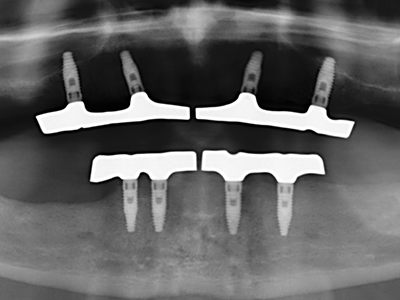

Para la extracción de implantes es posible realizar la preparación de una tapa ósea vestibular que, tras retirar el tornillo del implante, vuelve a fijarse y, de este modo, mantiene el contorno de la apófisis alveolar.